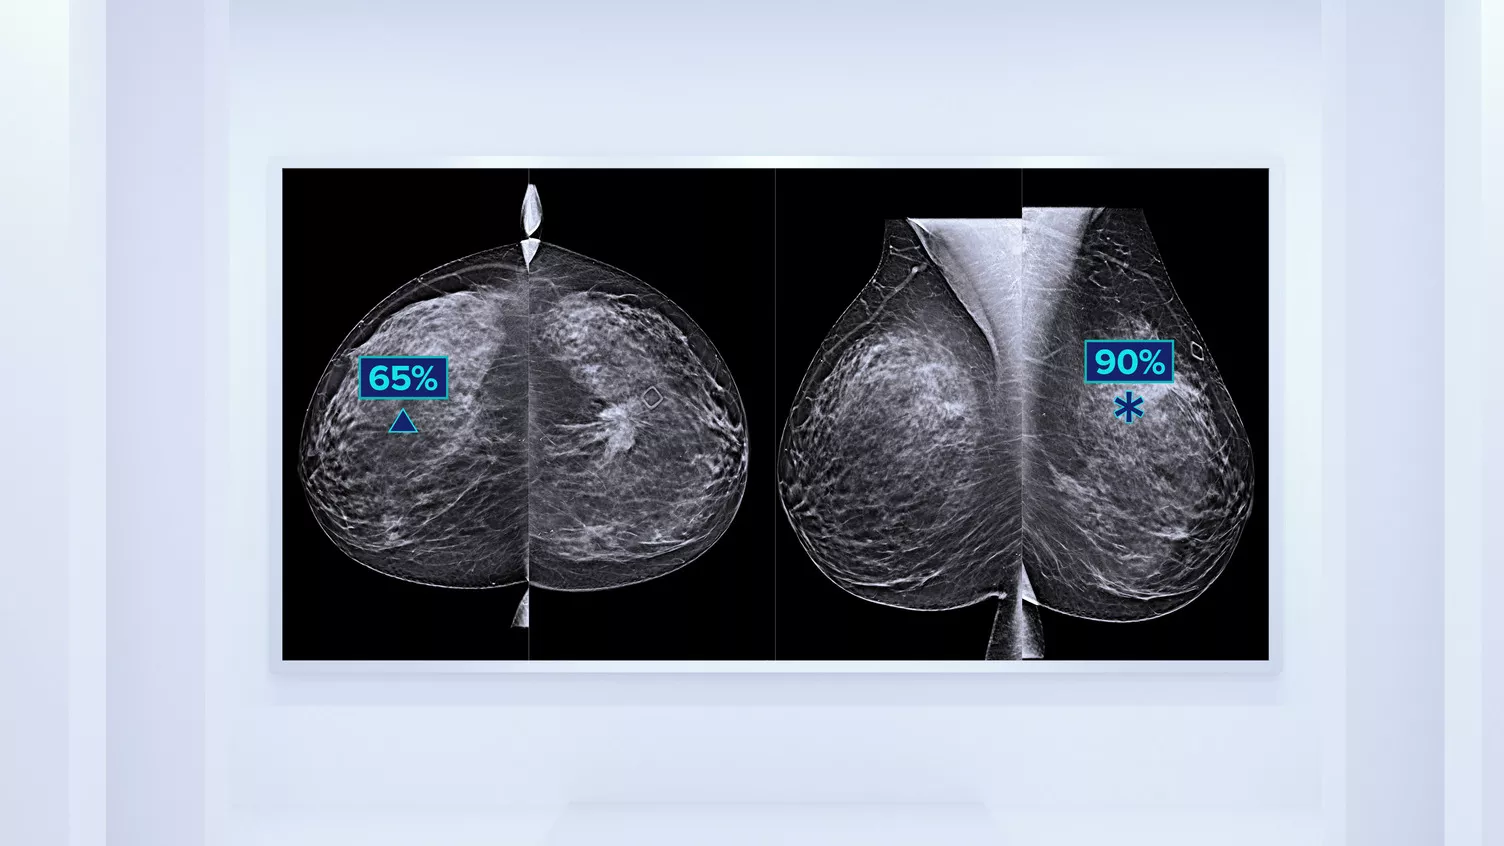

Genius AI™ Detection Technology

En deep-learning-algoritme designet til at hjælpe radiologers diagnostiske kapacitet og påvise brystkræft4,9,10 på tomosyntesebilleder fra Hologic Dimensions-mammografisystemer. Den lokaliserer læsioner ved at søge i hver skive af billedsættet. Mistænkelige områder fremhæves med henblik på samtidig aflæsning på arbejdsstationen.

Quantra™ Technology

Det vides, at meget tæt brystvæv øger en kvindes risiko for brystkræft.11,12 Behovet for nøjagtige, upartiske analyser er derfor afgørende. Quantra-softwaren er drevet af maskinlæring og analyserer brystvævets tekstur og mønster i både 2D- og tomosyntesebilleder og kategoriserer brysterne i fire risikokategorier for sammensætning.13